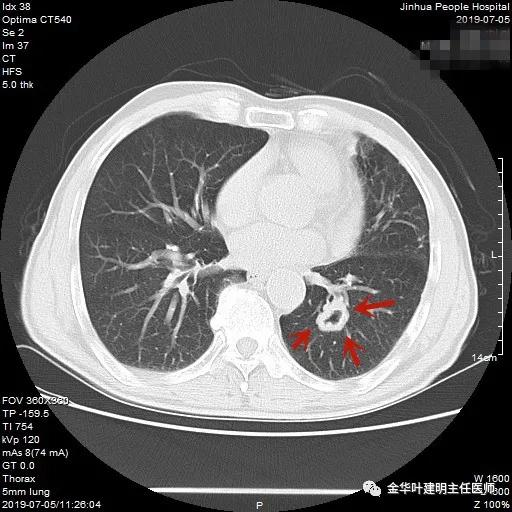

上图示鳞癌。病灶厚壁空洞,内壁凹凸不平,鳞癌可以乏收缩力,不一定有毛刺征或胸膜凹陷征。